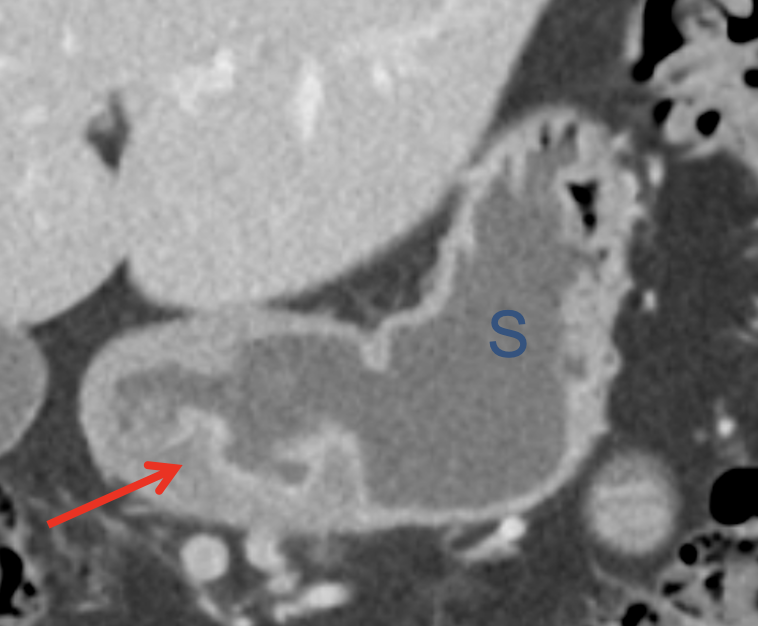

“In our patient, the findings of prominent mucosal folds extending from the pylonic channel on upper gastrointestinal series and the thickened antral wall on CT scans correlate well with the known pathologic appearance of gastnic antral vascular ectasia. Histologically, antral thickening results from a combination of foveolar and fibromuscular hyperplasia. Grossly, the antral fold prominence appears to result from bunching of the mucosa in the thickened, hypercontractile antrum.” Gastric antral vascular ectasia ("watermelon stomach"): radiologic findings. Urban BA, Jones B, Fishman EK, Kern SE, Ravich WJ. Radiology. 1991 Feb;178(2):517-8. |

Watermelon stomach (WMS), or gastric antral vascular ectasia (GAVE) ![]() |

“Gastric antral vascular ectasia primanily affects women (9:1 female-to-male ratio) aged 56-76 years, and is associated with liver cirrhosis (37%) and achlorhydnia (35%). The usual symptoms are iron-deficiency anemia and melena due to chronic gastrointestinal bleeding from the dilated, superficial, and easily traumatized vessels. Antrectomy is curative, but endoscopic treatment with heat probes or lasers has shown promise.” Gastric antral vascular ectasia ("watermelon stomach"): radiologic findings. Urban BA, Jones B, Fishman EK, Kern SE, Ravich WJ. Radiology. 1991 Feb;178(2):517-8. |